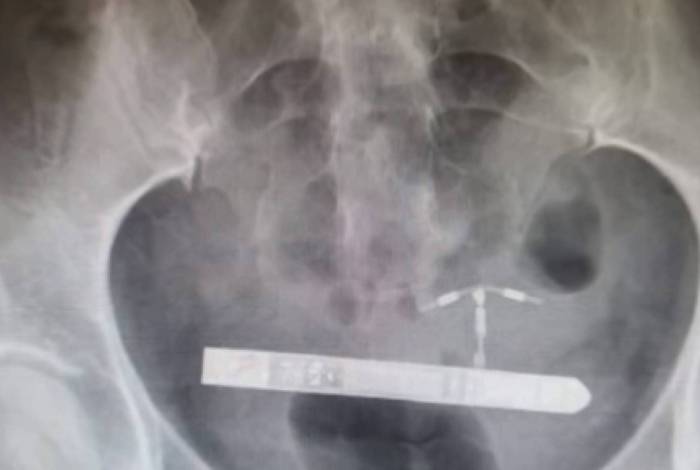

“Nós da equipe médica não conseguimos encontra-lo na vagina”, relembrou o ginecologista Greg Marchand. Em seguida, a mulher passou por um exame de raio x. “Fiquei surpreso quando percebi que ele estava na bexiga da paciente”.